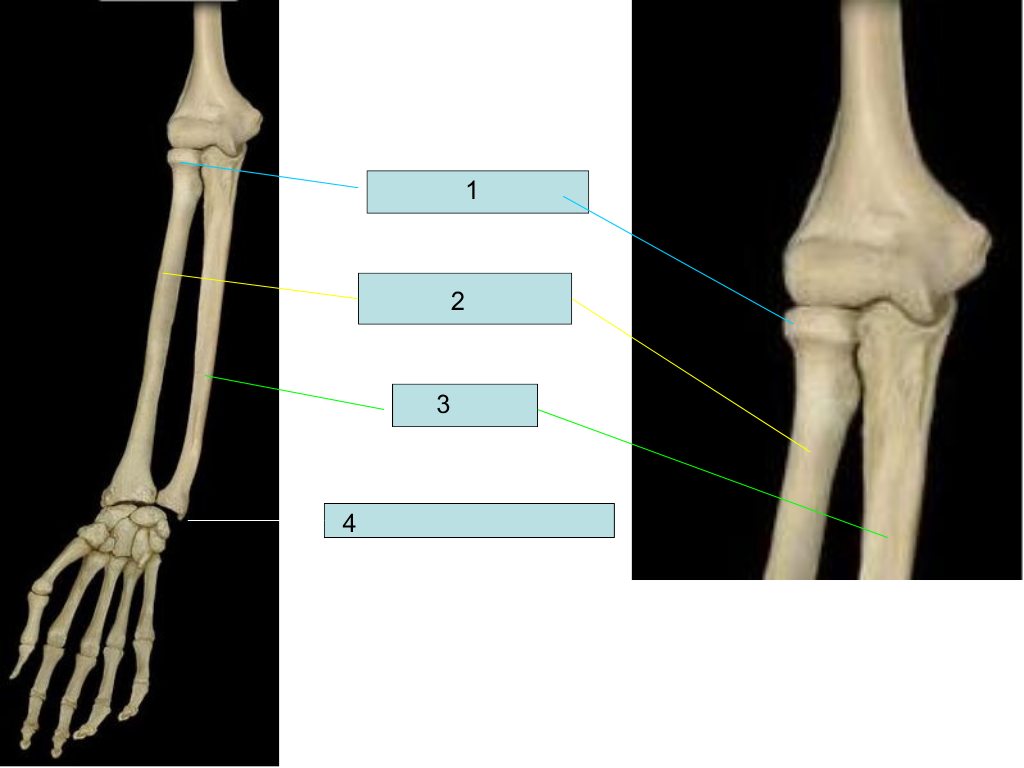

radial head

what is #1 pointing at?

radius

what is #2 pointing at?

ulna

what is #3 pointing at?

ulna styloid process

what is #4 pointing at?

olecranon process